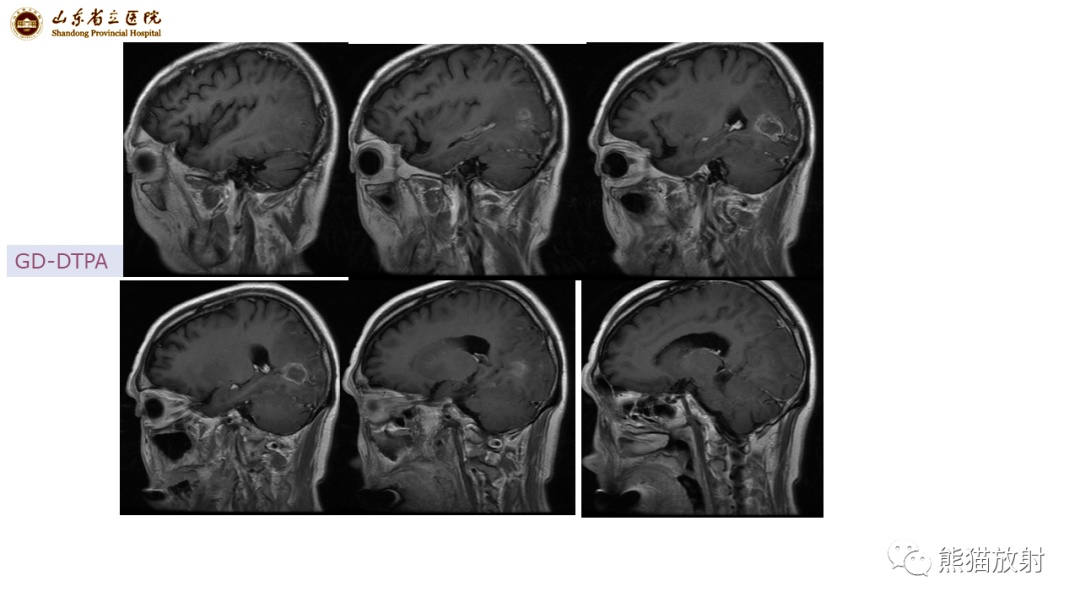

【病例】炎性肉芽肿并脓肿形成 & 成熟性囊性畸胎瘤-1